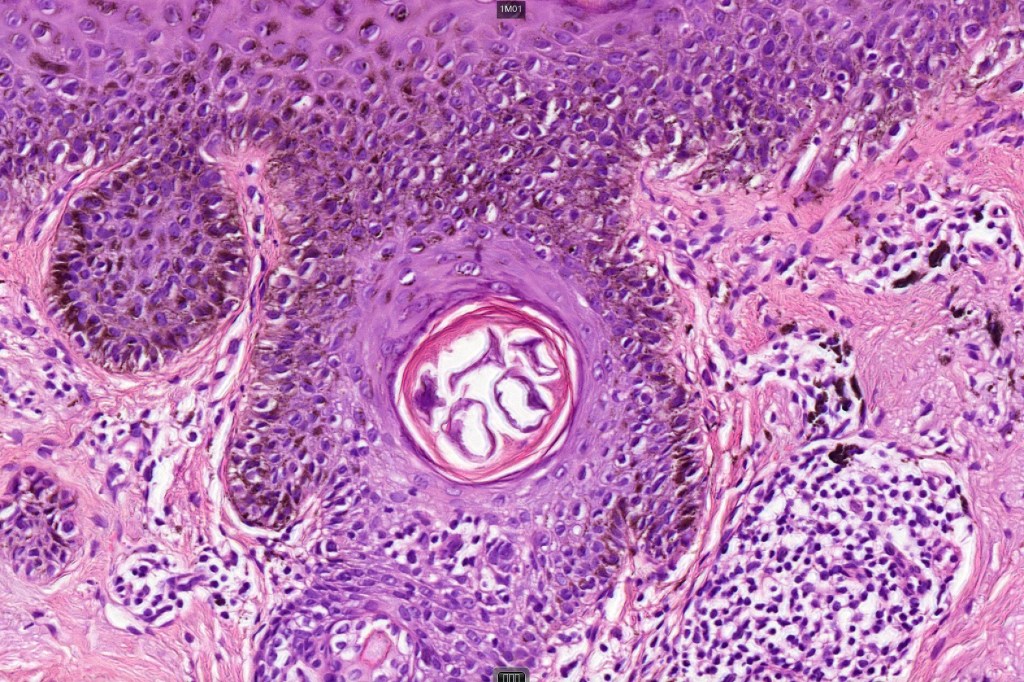

•Cytoplasmic retraction artifact, nuclear hyperchromatism with irregular borders

•Multinucleate giant cells

•Nest formation present in more advanced cases

•Dense melanin pigmentation may affect the whole epidermis making it difficult to determine which cells are melanocytes & which are keratinocytes! DAB-lablled antibodies should be avoided as they can be impossible to interpret

•Pagetoid spread